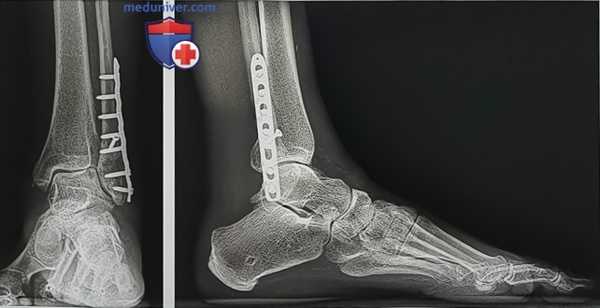

Рисунок 1

- Для оценки природы и локализации деформации (надлодыжечная, голеностопный сустав, подлодыжечная или сочетанная) выполняются рентгенограммы голеностопного сустава стоя в передне-задней проекции, стопы в боковой и передне-задней проекциях и заднего отдела стопы в проекции по Saltzman. Если клинически не исключается деформация на уровне коленного сустава или бедра, необходима рентгенография нижней конечности целиком (рис. 1)